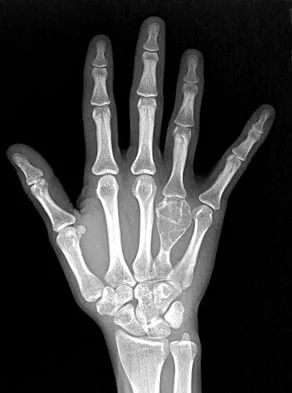

A 45-year-old man sustains a low-velocity gunshot wound to the base of the right thumb. The open wound is allowed to heal by secondary intention, resulting in a contracture of the first web space. Clinical photographs are shown in Figures 49a through 49c. Treatment should now consist of

The contracture is too large for a Z-plasty, which allows a 75% increase in length. Excision of the scar with placement of a skin graft is prone to contracture. A posterior interosseous fasciocutaneous flap will provide enough well-vascularized tissue and is well suited to reach the first dorsal web space. Buchler U, Frey HP: Retrograde posterior interosseous flap. J Hand Surg Am 1991;16:283-292.